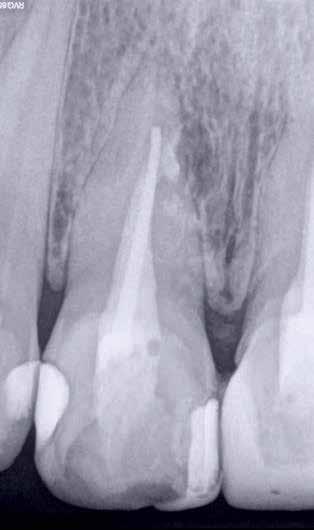

ai felvételek segítségével viszonylag jól el lehet különíteni a külső rezopció okozta ártalmaktól. A belső rezorpciótól szenvedő fogak esetében a radiológiai felvételek excentrikus irányból történő elkészítése során a rezorptív lézió a fog gyökércsatornájával egy irányba mozdul el a felvételen, míg külső rezorpció esetében le fog vetülni a gyökércsatornáról. 1999 márciusában egy 47 éves hölgy páciens arcduzzanattal kereste fel a rendelőnket. Klinikai vizsgálat során a jobb felső nagymetszőfog (11) kopogtatásra való érzékenységét tapasztaltuk. A felső front régióról készült periapikális felvételeken a frontfogakban lévő nagy kiterjedésű III. és IV. osztályú restaurátumokat észleltünk. Az 11-es fog gyökércsúcsa körül periapikális felritkulás volt látható. A 21-es fognál a gyökér középső harmadában belső rezorpciót észleltünk (13. ábra). A páciens kérdésünkre elmondta, hogy a bal felső nagymetszője közel 35 évvel ezelőtt traumás sérülést szenvedett. Mivel abban az időben CBCT-felvételek készítése nem volt számunkra elérhető, így a klinikai adatok alapján azt feltételeztük, hogy a rezorptív lézió bukkális irányba perforálta a gyökércsatorna falát, majd ezt követően az ezt a területet fedő bukkális csontállományt is destruálta.

A frontrégióban végzett szenzibilitás vizsgálat is megerősítette a 11 fogban a fogbélelhalás diagnózisát. Az 11-es fog endodonciai kezelése során a gyökércsatorna biokemo-mechanikai megmunkálását követően a gyökércsatornát meleg vertikális kondenzációs technikával zártuk. A bal felső nagymetsző esetében a gyökércsatorna megmunkálását a rezorpciós üreg koronális határáig végeztük, majd a megmunkált csatornaszakaszt fehér MTA-val töltöttük fel (14. ábra). Amennyiben ennek a fognak a kezelését ma kellene elvégezni, akkor az EndoSequence BC puttyt (Brasseler) használnánk a gyökértömés elkészítésére. Ezenkívül azt is megemlítenénk, hogy manapság egyre gyakrabban próbál-

13. ábra: A periapikális felvételen jól lekövethető a 11-es fog gyökércsúcsa körül látható radiolucens terület körvonala. A 21-es fog gyökerének középső harmadában pedig belső rezorpció jelenlétére utaló jelek észlelhetőek. A rezorptív lézió frontális és laterális irányban is áttörte a csontos falakat, amely következtében a gyökeret körülvevő csontállomány is károsodott. – 14. ábra: A posztoperatív felvételen jól megfigyelhető a 11-es fogba helyezett gyökértömés. A 21-es fog ellátása során a gyökércsatorna megmunkálását csak a rezorptív defektus koronális határáig végeztük. A gyökércsatorna zárására fehér MTA-t alkalmaztunk. – 15. ábra: A 11-es fog gyökércsúcsa körül látható felritkulás teljesen eltűnt. A rezorptív defektus mérete csökkent, valamint a rezorpciós üreg csontosodására utaló jelek is megfigyelhetőek. – 16. ábra: A saggitalis irányú CBCT-metszeten jól látható, hogy a 21-es fogat ép és jól megtartott bukkális kortikális csont fedi. A rezorpciós üreg mérete jelentősen csökkent, valamint az üreg kalcifikálódott anyaggal való telődése is megfigyelhető volt.

koznak a rezorptív léziók injektálható PRF-fel történő kezelésével. Az eddigi eredmények alapján ezzel az eljárással rendkívül kedvező hosszú távú eredményeket lehet elérni. A 21 évvel később készített kontrollfelvételeken látható, hogy az 11-es fog gyökércsúcsánál látható periapikális lézió teljesen eltűnt, valamint a rezorptív lézió mérete is jelentősen csökkent (15–16. ábra)